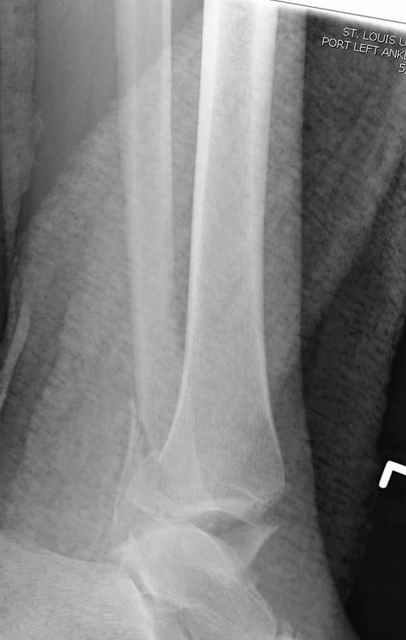

Pilon fracture:

где исследования на трупах показали, что малоберцовая кость участвует в стабильности голеностопного сустава, поддерживая наклон тарана (talar tilt) за счет связок. После ознакомления работой Ramsey в ортопедию ввели термин "при переломах голеностопного сустава смещенная

таранная кость следует за малоберцовой костью" т.е. связка не рвется, а тянет таран за собой, поэтому восстановление малоберцовой кости в

первую очередь, затем остальных элементов - стал классическим при лечении данной патолгии. Латеральная колонна (столб), дистальный

конец малоберцевой кости, к нему прикрепляется латеральный суставной фрагмент дистального эпиметафиза большеберцовой кости (как на снимке)

и таранная кость, которые при репозиции малоберцовой кости репонируются автоматически.

Из работ Ramsey and Hamilton, Yablon et., укорочения на 1мм

малоберцовой кости, уменьшает на 42% контактную поверхность между

малоберцевой и таранной кости, которое в свою очередь приводит к

увеличению давления на остальные части суставной поверхности, что

является предпосылкой раннего артроза.